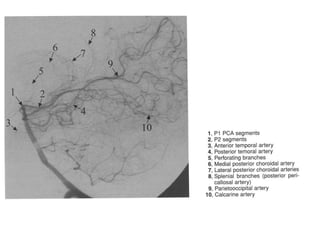

Segmentação da ACP

• P1(pré-comunicante): estende-se da bifurcação da AB até a

junção da AComP. Nos casos de padrão não fetal, P1 é mais

calibroso que a AcomP.

• Os ramos relativamente constantes de P1 são:

• Artéria talamoperfurantes, que entra no encéfalo pela

substância perfurada posterior.

• Artéria coroidea póstero-medial ( dirige para III ventrículo e VL)

• Ramo para a placa colicular.

• Ramos para o pedúnculo cerebral e segmento do mesencéfalo.

• Segmento P2: começa na AComP, percorre cisterna

crural e circundante.

• É divida didaticamente em P2A ou segmento curral ou

peduncular, pois envolve o pedúnculo cerebral na

cisterna curral.

• O segmento P2P ou circundante, continuação de P2A.

• Segmento P3 ou colicular: projeta-se posteriormente a

partir borda posterior da superficie lateral do

mesencéfalo, alcançando a cisterna colicular.

• Segmento P4: incluem ramos que se dirigem para a

superfície cortical.

Ramos corticais

• 1) Artérias temporais inferiores

• 2) Artéria temporal anterior

• 2) Artéria hipocampo

• 3) Artéria temporal média

• 4) Artéria temporal posterior

• 5) Artéria calcaria

• 6) Artéria comum

• 7) Artéria do esplênio